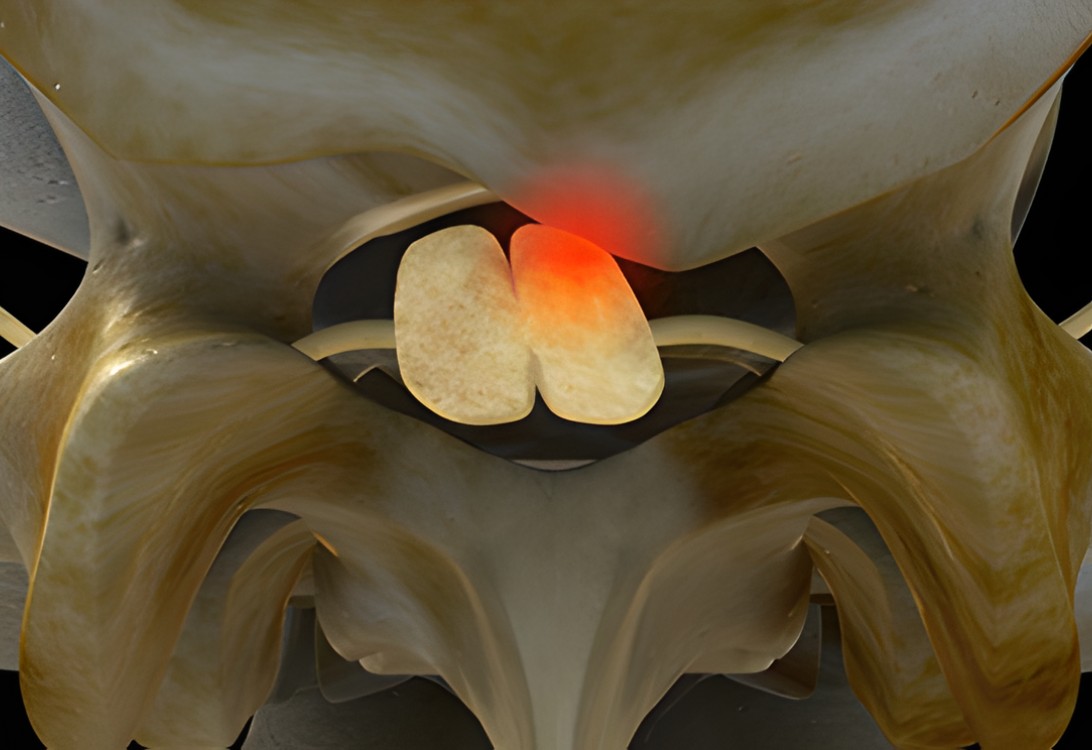

자생 비수술 한방통합치료 후

터진디스크가 흡수된 모습

비수술 치료만으로

터진 디스크 흡수

튀어나온 디스크 대비,

터진 디스크 치료 효과 우수

디스크 흘러내린 정도가

심할수록 흡수 가능성 증가